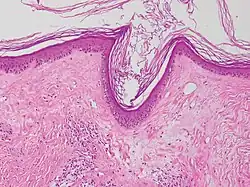

![]() Microfotografía de liquen escleroso que muestra la esclerosis subepitelial característica (derecha/abajo de la imagen). Tinción hematoxilina-eosina. | ||

Se puede hacer una biopsia de la piel afectada para confirmar el diagnóstico. Cuando se hace una biopsia, la hiperqueratosis, la epidermis atrófica, la esclerosis de la dermis y la actividad de los linfocitos en la dermis son hallazgos histológicos asociados con LS.[21] Las biopsias también se revisan para detectar signos de displasia.[22]